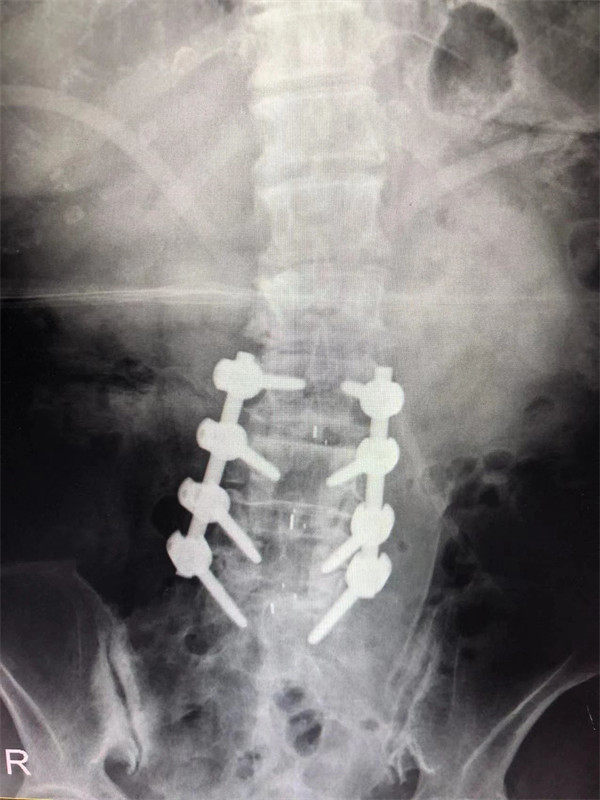

戈才華主任團隊討論病情及手術(shù)風(fēng)險,并與麻醉科醫(yī)生多次討論術(shù)中麻醉風(fēng)險,經(jīng)過詳盡周密的布置之后,最終給阿婆在全麻下進行腰3/4,4/5,腰5/骶1腰椎椎體間融合術(shù)。

手術(shù)后↓